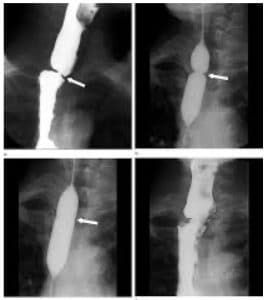

Υδροστατικοί διαστολείς με συρμάτινο οδηγό. Οι διαστολείς αυτοί διέρχονται εύκολα από τον υποφάρυγγα και χρησιμοποιούνται με εξαιρετική ασφάλεια, λόγω της χρήσης του συρμάτινου οδηγού. Είναι λίαν ατραυματικοί και εφαρμόζονται για στενώσεις σε όλο τον πεπτικό σωλήνα. Το αποτέλεσμα της διαστολής ελέγχεται με την ακτινοσκοπική επιτήρηση της κλεψύδρας, η οποία σχηματίζεται στην περιοχή της στένωσης.

Πριν από κάθε διαστολή προηγείται η ακτινολογική μελέτη της στενεμένης περιοχής με αραιό βάριο. Αξιολογούνται η μορφολογία της στένωσης και τα χαρακτηριστικά της, όπως για παράδειγμα: η θέση, το μήκος, το εύρος, καθώς και το αν είναι συμμετρική ή έκκεντρη. Μελετάται το περιφερικό τμήμα του οισοφάγου, της γαστροοισοφαγικής συμβολής, του στομάχου και του δωδεκαδακτύλου, ιδίως όταν δεν είναι εφικτή η διέλευση του λεπτού ενδοσκοπίου μέσα από τη στένωση.